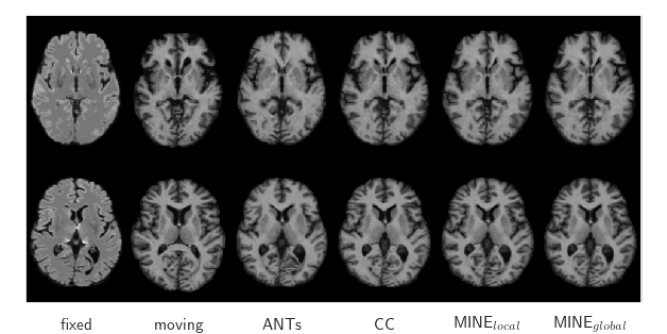

Representative registration results are shown in Fig. 3. All methods produce accurate results on both tasks with minor differences in varying locations. Ignoring the extracortical differences resulting from background masking in the atlas, the most prominent differences for all methods are in the cortex where the largest inter-patient anatomical variation occurs, though differences in the lateral ventricles are also visible. In the mono-modal task these differences are consistent throughout the image for ANTs and MINE while VM-CC shows larger average misalignment in the frontal lobe, and especially the anterior horn of the lateral ventricles, compared to the rest of the image. This is consistent for all values of in all similarity metrics evaluated. We hypothesize that intensity normalization in small neighborhoods for CC, while producing excellent overall results, can have a negative effect on learning features for registration where there is large anatomical variation. Since MINE is a global metric, even in our local sampling strategy, it does not suffer from this variation. The difference images also show that MINE behaves consistently everywhere with minimal differences on sub-structure boundaries where voxel intensities change.